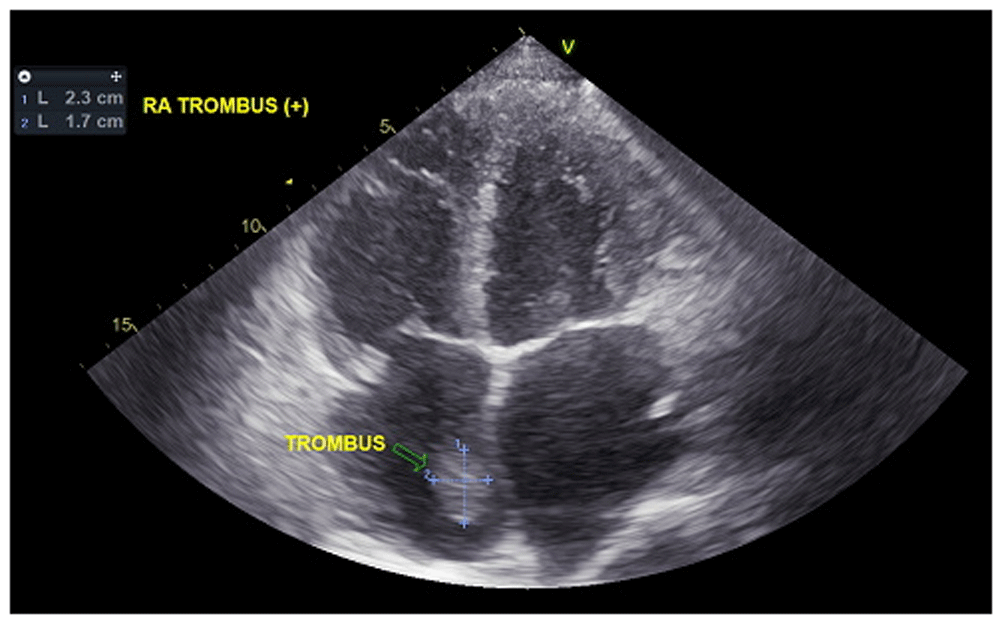

In laboratory findings, serum electrolytes revealed hypokalemia (K: 3.3 mmol/L; normal range 3.5–5.1 mmol/L), serum protein showed hypoalbuminemia (albumin: 3.1g/dL; normal range 3.4–5.0 g/dL), while other parameters were between normal limits. An electrocardiogram (ECG) showed sinus tachycardia rhythm 125 bpm, right-sided frontal axis, horizontal axis clockwise rotation, and slow progression of R waves at V1–V4 (Figure 1). A chest X-ray showed cardiomegaly, pulmonary congestion, and minimal bilateral pleural effusion (Figure 2). Echocardiographic examination revealed moderate mitral regurgitation (dilated mitral annulus), dilatation of all cardiac chambers (LVIDd 5.8 cm), visible thrombus in IVC to RA, decreased left and right ventricular systolic function (EF teich 35%, TAPSE 1.3 cm), and global hypokinetic of the left ventricle with eccentric LVH. The scans from a transthoracic echocardiogram (TTE) showing thrombus is shown in Figure 3 and Figure 4.

A chest CT scan (Figure 5) showed right pulmonary artery embolism at ± 5.9 cm from bifurcation on the anterior side of the intermediate right bronchus; emboli on the left pulmonary artery bifurcation and the left pulmonary artery basal part; multiple right intraatrial hypodense lesions not showing contrast enhancement leading to a visualization of the right intraatrial thrombus; pulmonary infarction in the lateral-posterior segment of the base of the inferior lobe of the right lung, the lateral-posterior segment of the base of the inferior lobe of the left lung, and the anterior segment of the superior lobe of the left lung; and superior vena cava thrombus at VTH level 1-5. Figure 6 shows the protruded thrombus in the right atrium passing through the tricuspid valve. TTE also showed the position of the thrombus moving from the inferior vena ca va towards the right atrium (Figure 7). The movement of the large protruding thrombus can be seen in supplementary video files 1–35–7.